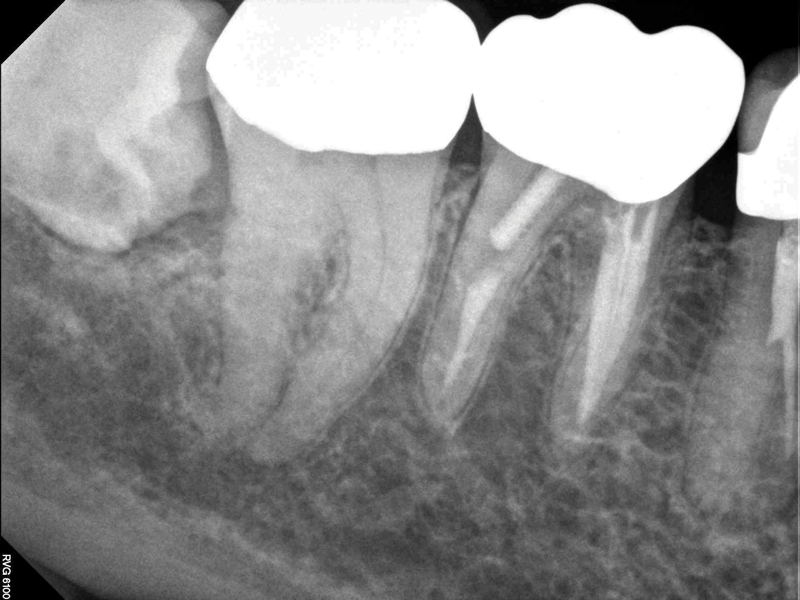

Although the patient's chief complaint was consistent with a degenerative pulpitis, the clinical and radiographic examination was initially unremarkable. All teeth in the maxillary and mandibular right quadrants were normally responsive to pulp sensitivity testing, and they were neither percussion nor palpation sensitive. Neither swelling nor sinus tracts were present, and the periodontal examination revealed normal probing depths and lack of mobility throughout the quadrant. Initial periapical radiographs revealed normal PDL spaces surrounding teeth Nos. 30 and 31, as well as a horizontally impacted No. 32 with a radiolucency within the crown in close proximity to the distal root surface of No. 31 (Figure 2 and Figure 3). Because the reported pain was severe, and in an effort to not only diagnose the issue but also offer some respite from the severe pain the patient was experiencing, an inferior alveolar nerve block was administered using 3.4 cc 0.5% bupivacaine with 1:200,000 epinephrine. Within 5 minutes of administration, the patient reported complete resolution of his pain.

Fig 2. Case 1: Periapical imaging of the maxillary right (Fig 2) and mandibular right (Fig 3) quadrants initially showed no obvious pathology, aside from the horizontally impacted tooth No. 32. Secondary imaging following successful relief of pain after administration of an inferior alveolar nerve block revealed pre-eruptive intracoronal resorption in tooth No. 32 with resultant symptomatic irreversible pulpitis as the likely source of pain (Fig 4).

Figiure 2

Fig 3. Case 1: Periapical imaging of the maxillary right (Fig 2) and mandibular right (Fig 3) quadrants initially showed no obvious pathology, aside from the horizontally impacted tooth No. 32. Secondary imaging following successful relief of pain after administration of an inferior alveolar nerve block revealed pre-eruptive intracoronal resorption in tooth No. 32 with resultant symptomatic irreversible pulpitis as the likely source of pain (Fig 4).

Figure 3